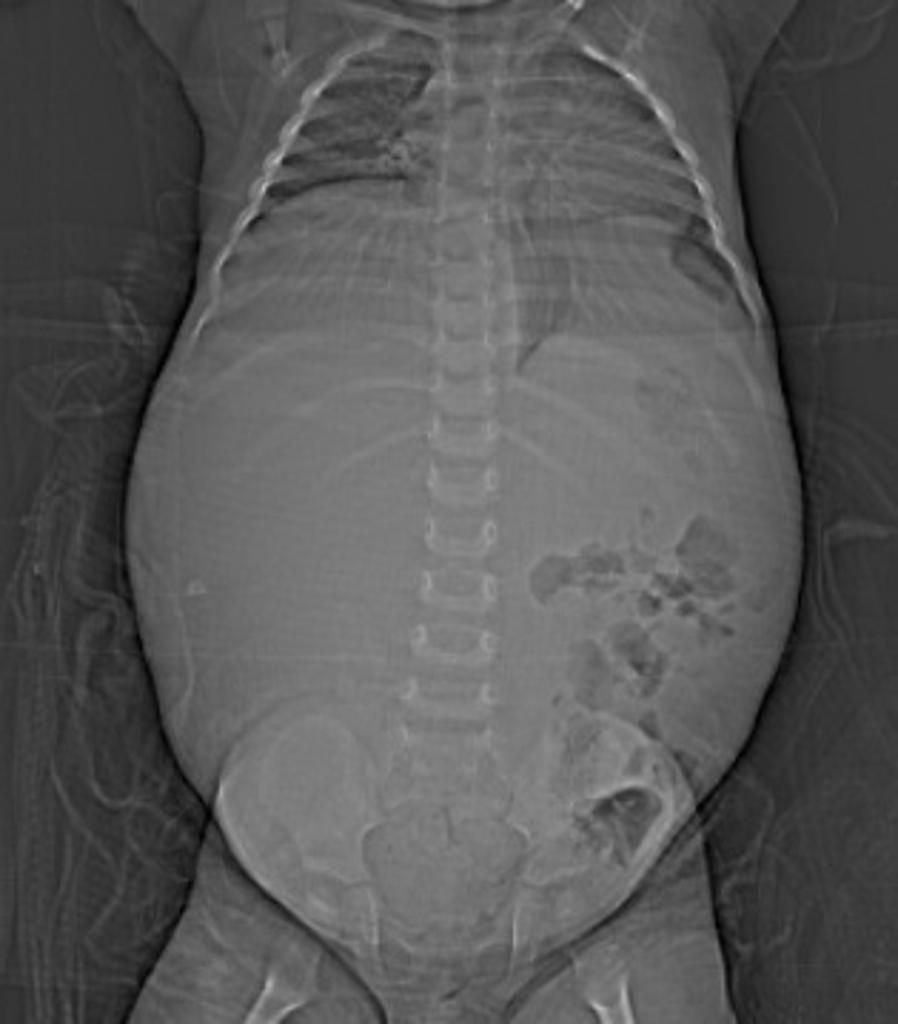

الثانيه: wilm's tumor (nephroblastoma)

🌐اشيع ورم لدى الاطفال.

🌐عاده يكون في جانب واحد.

السبب:

Autosomal Recessive في الكروموسوم 11

يعيش الطفل من ٢-٥ سنين.

من الأعراض:

👦🏻يظهر ككتله في البطن.

👦🏻إرتفاع ضغط الدم.

👦🏻٩٠% منهم بيعيشوا ٥ سنين.